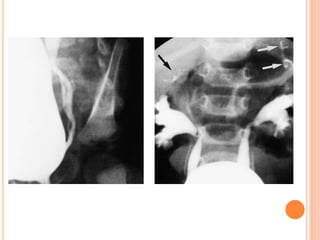

VOIDING

CYSTOURETHROGRAPHY

VCUG is commonly performed in children

with prenatally diagnosed hydronephrosis,

urinary tract infections, and voiding

abnormalities.

The procedure should include assessment

of the spine and pelvis; masses or opaque

calculi; bladder capacity, contour, and

emptying capability; presence and grade of

reflux; and urethral appearance.